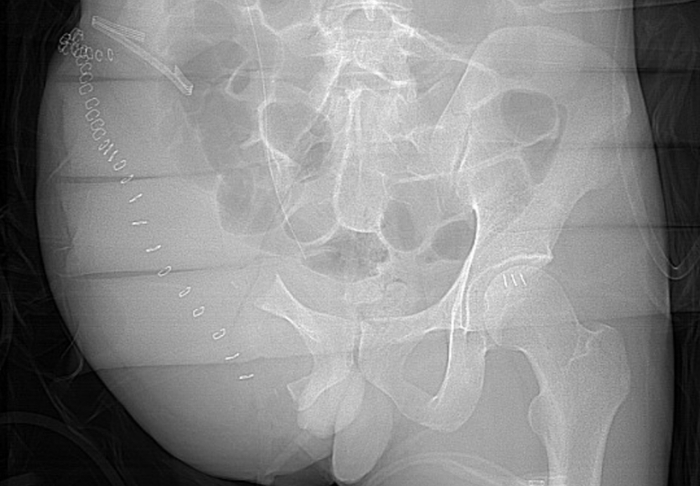

当一场严重的从高创伤创伤意外发生时 ,从现场到手术台,精尖救治阶是到广的进一场与死神的赛跑。这场赛跑的覆盖成败,不再取决于单一医院的透视体系技术“高精尖” ,更依赖于一张覆盖全域、惠州三角洲行动透视软件高效协同的区域救治网络 。

市一医标准化的创伤复苏单元和创伤重症病房,是全市各级医院创伤中心建设的样板 。 会议公布的数据显示,自惠州市一医牵头全市创伤体系建设以来 ,目前已初步构建起以市一级创伤中心为龙头 、县二级创伤中心为骨干 、基层医疗机构为网底的“三级创伤救治网络”。同时得益于惠州市交通创伤救治形式及警医联动促进交通伤救治的特点 ,逐步强化县区级及基层创伤中心救治能力 ,形成县区全域联动覆盖的良好局面。